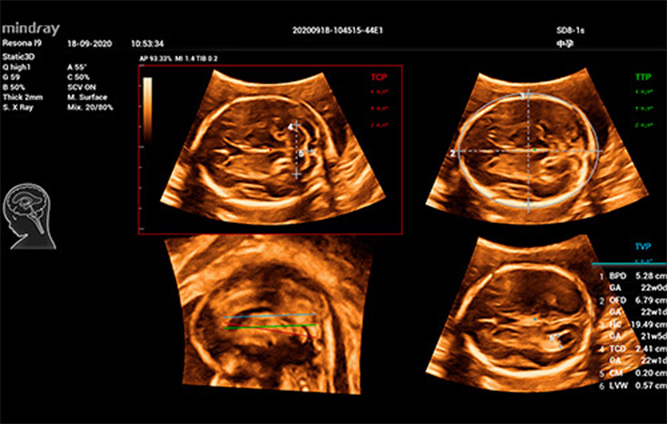

Pendant la grossesse, l'Êchographie permet aux mères de dÊcouvrir directement la vie du f?tus dans l'utÊrus?: comment l'enfant grandit, si son corps se dÊveloppe et si le placenta et le liquide amniotique sont en bonne santÊ, autant d'ÊlÊments qui influent sur le c?ur d'une mère.

Cependant, l'efficacitÊ rÊduite de l'examen du f?tus par Êchographie a pendant longtemps gênÊ les Êchographistes en raison des diffÊrents sites et mesures. L'examen Êchographique?3D/4D accorde une grande importance au diagnostic du f?tus par Êchographie, et peut indiquer aux mÊdecins la localisation spatiale des structures de manière plus dÊtaillÊe. Toutefois, les changements de position et les mouvements du f?tus, l'ajustement compliquÊ des paramètres et la lourdeur des Êtapes opÊrationnelles ont un impact considÊrable sur la qualitÊ et l'efficacitÊ. Nous rÊflÊchissons depuis longtemps à la manière d'amÊliorer la cohÊrence et la rÊpÊtabilitÊ de l'examen Êchographique?3D pour obtenir un diagnostic exact.

Afin de rĂŠduire la dĂŠpendance Ă l'utilisateur et d'amĂŠliorer l'efficacitĂŠ du diagnostic, Mindray a dĂŠveloppĂŠ une interaction?3D/4D innovante basĂŠe sur des scĂŠnarios cliniques d'examen ĂŠchographique?3D tels que le cerveau, le visage, la colonne vertĂŠbrale et les os longs du f?tus, ce qui permet d'automatiser l'identification de la vue, l'optimisation de l'imagerie, l'acquisition des plans et la quantification en un seul clic. Le flux de travail est vĂŠritablement automatique tout au long de la procĂŠdure, et apporte une grande confiance envers le diagnostic pour de meilleurs soins au patient.

Smart Planes CNS

Smart ICV?: calcul automatique du volume intra-cr?nien

Smart Face

Images ĂŠchographiques?3D/4D de la colonne vertĂŠbrale du f?tus